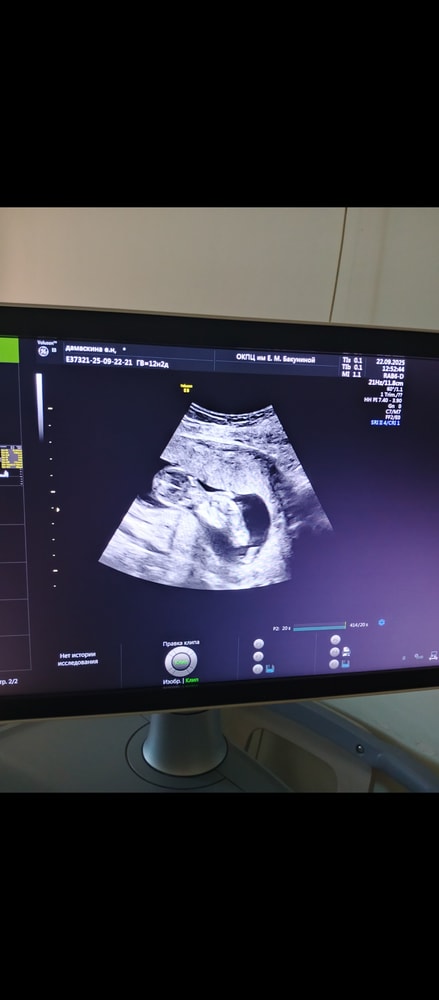

Как думаете девочка или мальчик?

Кто в животике живёт (гадаем по фото УЗИ; результаты НИПТ или УЗИ)Как думаете, девочка или мальчик?

Как думаете, девочка или мальчик?